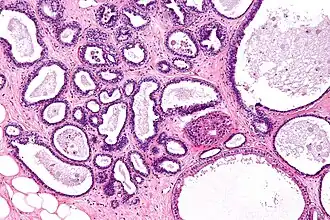

Description de cette image, également commentée ci-après

Histologie de la mastopathie kystique diffuse

La mastose ou mastopathie kystique diffuse est un terme qui englobe un certain nombre de lésions histologiques bénignes non cancéreuses et non inflammatoires.

La mastopathie kystique diffuse se caractérise par l'apparition, dans les deux seins, de formations kystiques régulières, sans attache avec le tissu sous-jacent.